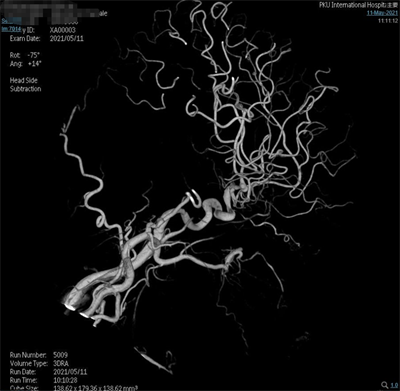

辅助检查:头部CT(外院,2021-4-25):左侧基底节区脑出血破入脑室,蛛网膜下腔出血。脑动脉造影(外院,2021-5-10):双侧大脑中动脉分叉处动脉瘤,动脉瘤形态不规则。

脑动脉造影(外院,2021-5-10):双侧大脑中动脉分叉多发动脉瘤。

夹闭前造影